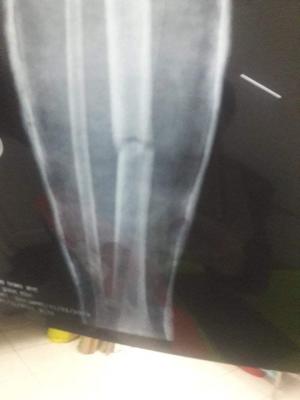

- Chân phải cháu bị gảy ngang, hiện tại đã nắn và bó bột

Khoảng 20h00 tối thứ 7 cháu đi cùng ông nội từ siêu thị về nhà không may bị tai nạn, người gây tại nạn say rượu nên đâm thẳng vào xe 2 ông cháu, cháu Nam sau khi được mọi người đưa vào bệnh viện Tĩnh bác sỹ kết luận bị gảy chân, Chấn thương sọ não, Tụ máu não nên phải chuyễn gấp vào bệnh viên TW Huế